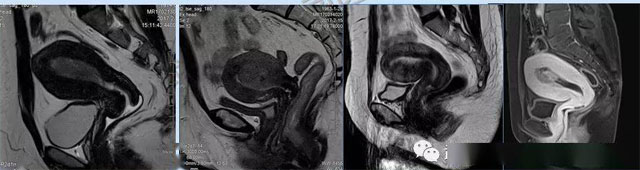

婦科疾病常常讓女性陷入了焦慮。主要是這類(lèi)疾病婦女有難言之隱,癥狀隱匿,病情復(fù)雜。磁共振體檢車(chē)的金光火眼能力可以破解各種婦科難題。哪些情況需要使用磁共振檢查,檢查過(guò)程是否有不適。這些都是可以解決的。例如子宮常見(jiàn)疾病的磁共振診斷。

磁共振VS傳統(tǒng)檢查:有這些優(yōu)勢(shì)?無(wú)輻射安全系數(shù)高,磁共振沒(méi)有電離輻射,適合備孕跟孕婦檢查。它對(duì)軟組織有高清的成像效果,可以清晰的看到子宮各層的結(jié)構(gòu)??梢宰R(shí)別細(xì)小的肌瘤,早期的癌癥腫瘤??梢园l(fā)現(xiàn)其他設(shè)備難以檢查到的深部子宮內(nèi)膜異位結(jié)節(jié)。多序列成像和增強(qiáng)掃描檢查,判斷腫瘤的良性準(zhǔn)確率高達(dá)90%以上。